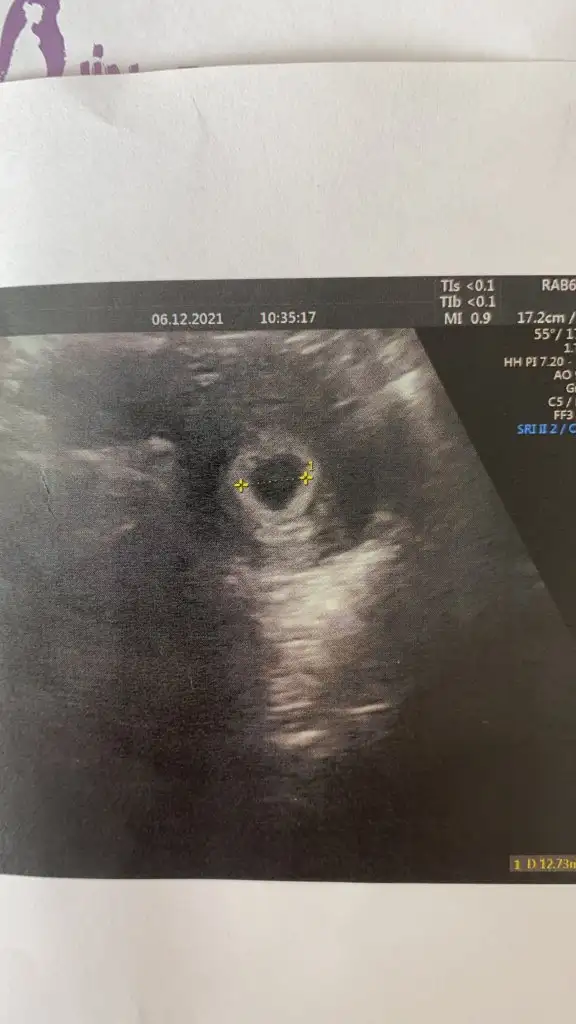

Kızlar bugün tüp bebek doktorum dışında başka bir doktora gittim 5+3 günlük gebelik gözüktü kese düzgün herşey güzle kanama alanı yok dedi gerekirse 3 günde bir pruluton vururuz dedi bu lekelenmeler olabilir çok normal dedi kılcal damarları zedeliyor olabilir bebek büyüdükçe dedi tam transfer tarihim ile uyumlu çıktı haftaya kalp atışı için çağırdı vajinal bakmadı geç duyalım ses riske atmayalım yeterki dedi mükemmel bir doktora rastladım çok mutluyum şuan moralmen 10 numarayım